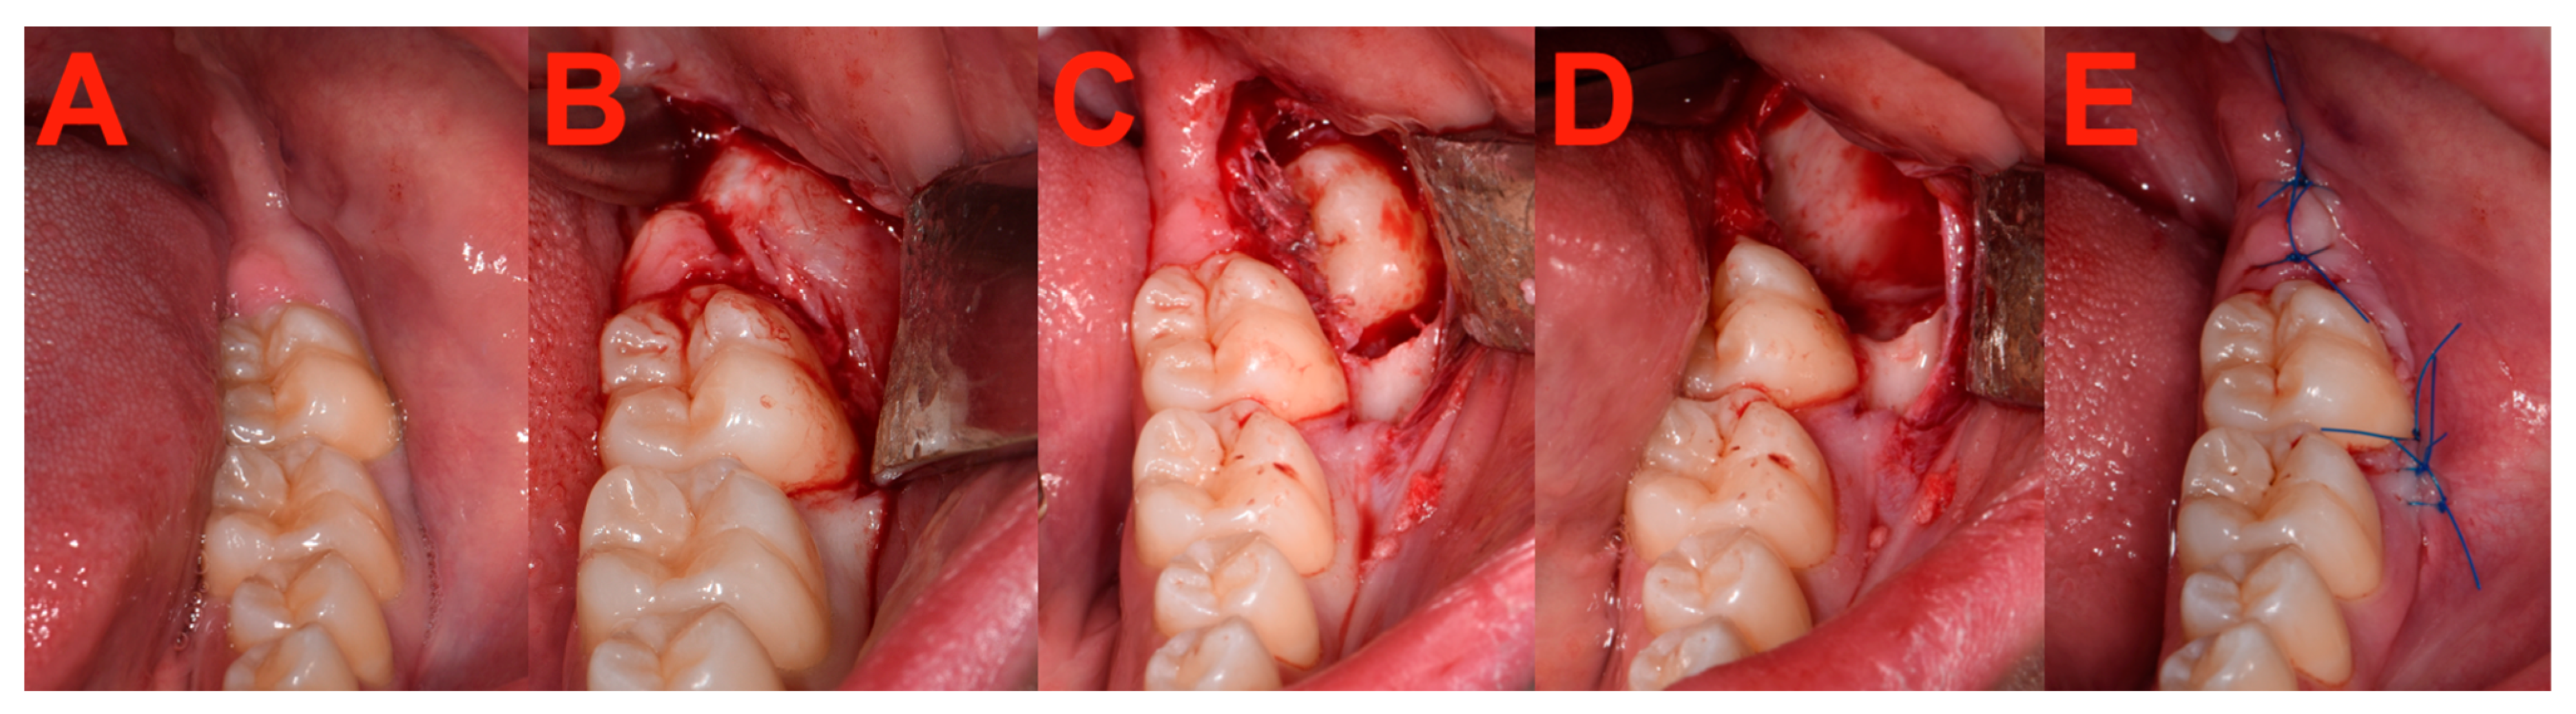

2.7. Surgery

2.3. Clinical Patients

2.3.1. Eligibility/Inclusion Criteria